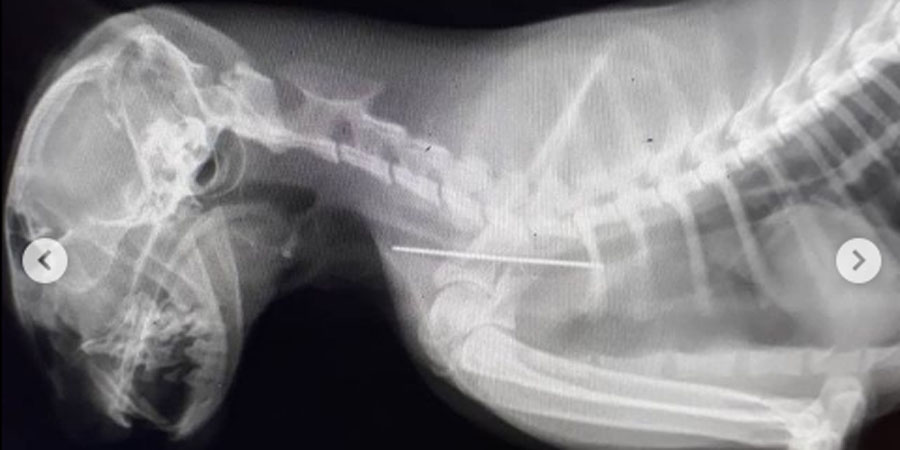

Рентгенография показала, что у животного между пищеводом и трахеей застряла игла. Кошке провели срочную операцию по удалению инородного тела. Сейчас животное проходит послеоперационное лечение и чувствует себя хорошо.